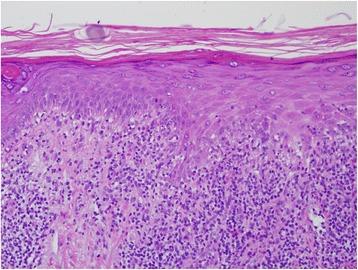

Seventy-three year old female with a diagnosis of stage IV breast cancer undergoing management with capecitabine presents with a rash during the summer months that is biopsy proven to be lichenoid photosensitive rash with likely offending agent being capecitabine. Her treatment was initially held despite having response to treatment, started on topical steroids after evaluation by dermatology. Given her response to treatment, drug was resumed with instructions to use sun precaution, sunscreen, and to complete course of topical steroids until rash resolution.

一名 73 岁女性,诊断为 IV 期乳腺癌,接受卡培他滨治疗,在夏季出现皮疹。皮疹活检证实为苔藓样光敏性皮疹,可能的致病药物是卡培他滨。尽管治疗有反应,她的治疗最初还是被暂停了,并在皮肤科评估后开始使用局部皮质类固醇。鉴于她的治疗反应,在给予使用防晒措施、防晒霜和完成局部皮质类固醇疗程直至皮疹消退的指示后,恢复了药物治疗。